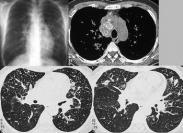

• 肺轉移性腫瘤

628健康網為您分享有關肺轉移性腫瘤的癥狀,肺轉移性腫瘤的治療方法,肺轉移性腫瘤的預防知識,肺轉移性腫瘤的癥狀圖片,肺...